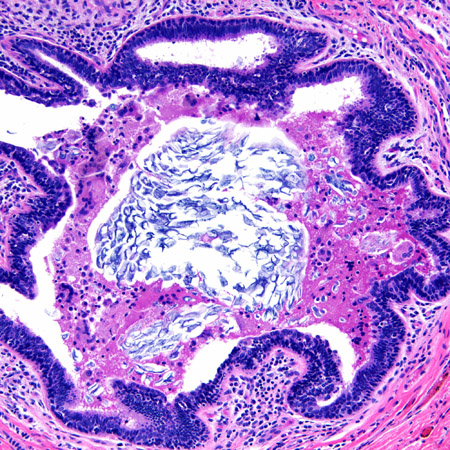

Duct ectasia with a central calcified keratin plug and associated giant cell inflammatory response

From the collection of Liron Pantanowitz, MD, Tufts University School of Medicine, MA